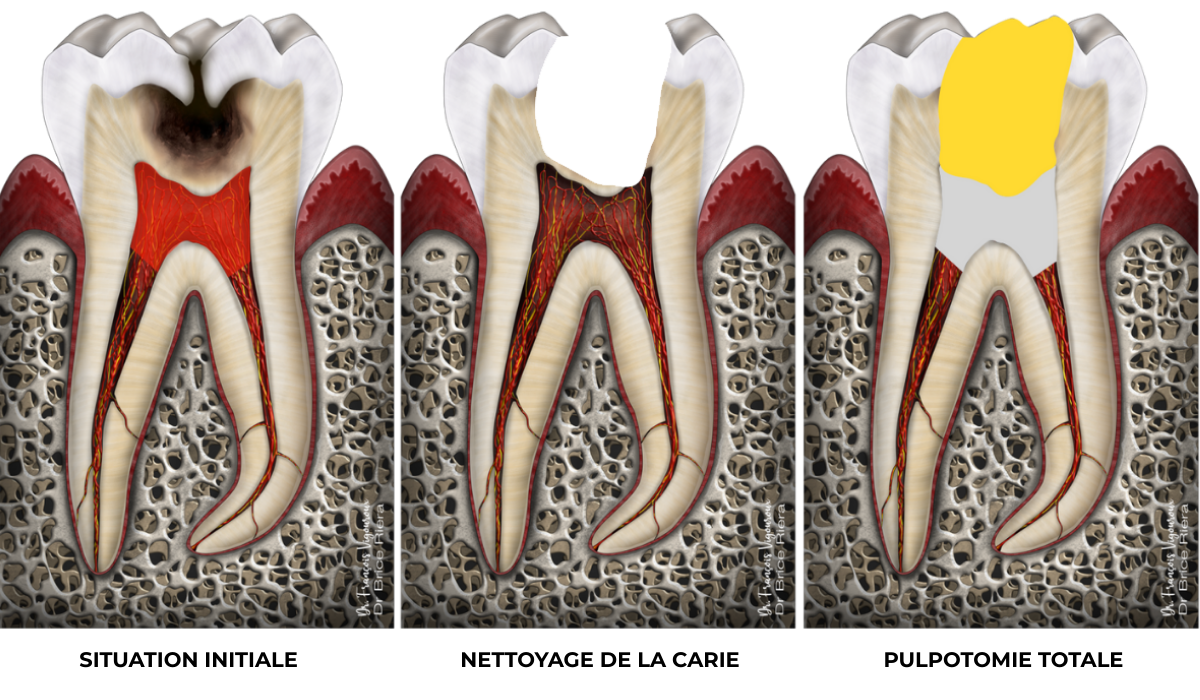

Pulpotomie camérale

Que ce soit lors du diagnostic, ou lors de l’intervention, il est possible que la pulpe camérale ne soit pas conservable. La pulpe camérale est la pulpe située dans la chambre pulpaire (schéma de gauche en rouge transparent).

A droite en jaune matériau de restauration coronaire / en gris : biomatériau bioactif (type ciment biocéramique)

Cas clinique

Pulpotomie totale : 91,3% de taux de succès